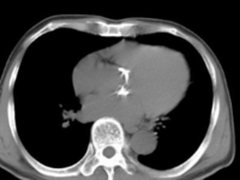

2017-05-11 关键字:大多数患者在童年期不呈现明显临床症状,直到进入青年期才开始表现出易疲乏,劳累后气急、心悸等症状。且对肺循环压力升高的病人更加容易反复发作,引起呼吸道感染和肺炎等疾病的发生,需及时对患者进行手术治疗,即......